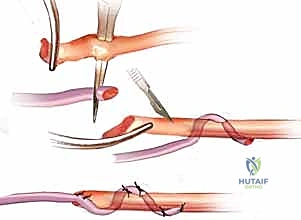

Tendon Weave Junctures: The Pulvertaft Technique

When performing a tendon transfer or graft, the juncture must be robust. The Pulvertaft end-weave technique is our standard.

TECH FIG 1 • End weave technique. The smaller tendon is passed through and sutured.

Technique:

1. Identify the donor and recipient tendons. The recipient tendon, if a stump, should be debrided to healthy tissue.

2. Using a pointed tendon-grasping and passing instrument—a small curved Kelly clamp or a tendon passer works beautifully here—create a series of three weaves at right angles through the substance of the larger, recipient tendon.

3. For example, your first entry is horizontal, the next vertical, and the third horizontal. Each pass should be through the substance of the tendon, not just the paratenon.

4. Pass the donor tendon through these weaves.

5. Secure the weave with multiple non-absorbable sutures (e.g., 3-0 or 4-0 Ethibond or Fiberwire). We use a locking stitch technique to prevent pull-out. The goal is a broad, secure interface that allows for excellent healing and prevents gapping.

Surgical Warning: Ensure minimal trauma to the tendon substance during weaving. Excessive fraying can weaken the repair. The weave should be tight enough to prevent gapping but not so tight as to strangulate the tendon.